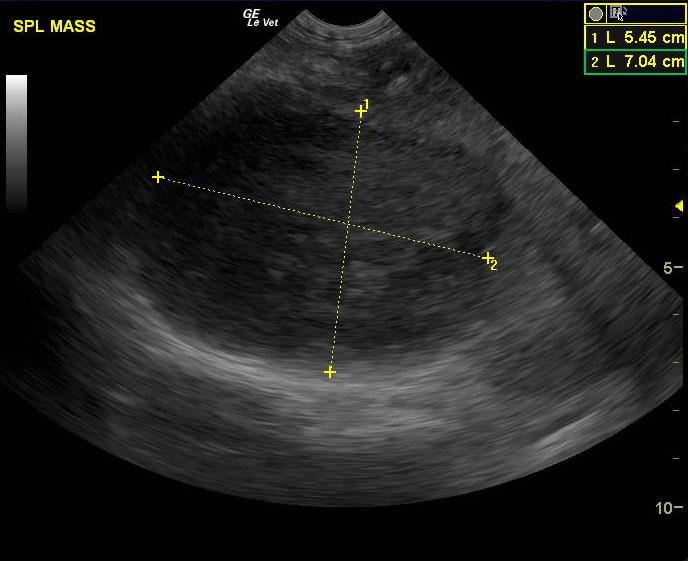

A 7 year old intact male pit bull terrier was presented for an abdominal tumor. Abnormalities on CBC and serum biochemistry were severe anemia and hypoalbuminemia.

A 7 year old intact male pit bull terrier was presented for an abdominal tumor. Abnormalities on CBC and serum biochemistry were severe anemia and hypoalbuminemia.